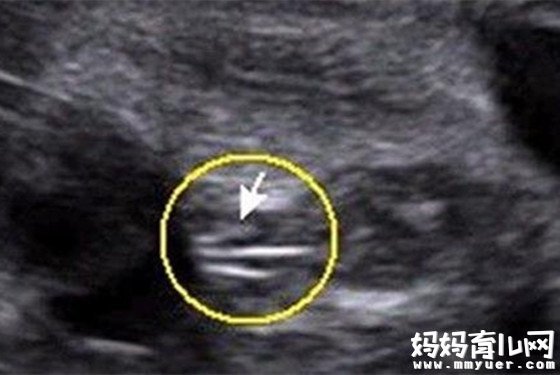

第三种:通过四维彩超图看清胎儿性别

男宝宝B超图

"凸出的东西"是他的标记:你们看到圆圆的是DANDAN,如果看到圆圆的加小肠的就是全部JJ